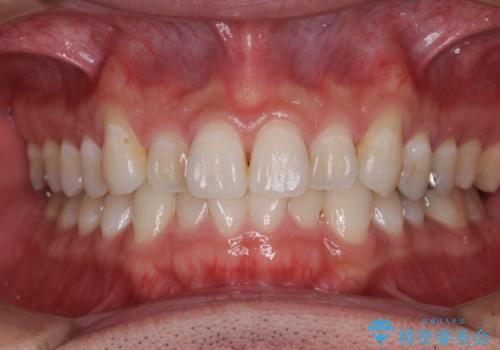

歯並びや奥歯の痛み 色々と治したい 総合歯科診療